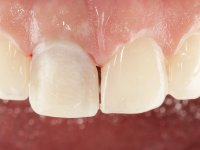

The patient was asked to remove the infiltrated crown and make a new crown with a ceramic-coated Zr infrastructure. As aesthetically, the crown was very well achieved, the patient and her dentist showed doubts about the need or not to intervene immediately. After clarifying my position on the infiltrated interfaces, we decided to jointly intervene. In these situations, the sooner you intervene the better

A pre-print was performed to make a crown in dual-cured resin. After a cross-section with a turbine, the infiltrated crown was removed with a microluxador. The dental stump was re-prepared to better define the shape and location of the cervical margin. It was necessary to place composite resin on the buccal surface of the provisional crown to improve its esthetics. The impression was made using a double-mix technique with two-viscosity, quick-setting silicones. In the laboratory, a crown with a ceramic-coated Zr infrastructure was made. After placing it in the mouth, we verified that the crown showed a greater translucency than the symmetrical one, not fulfilling our aesthetic goals. The ceramist had the opportunity to observe the situation in the clinic, collecting records for later rectification. The new crown was placed in the mouth and approved by the patient. The final cementation was done with resin-reinforced glass ionomer cement.